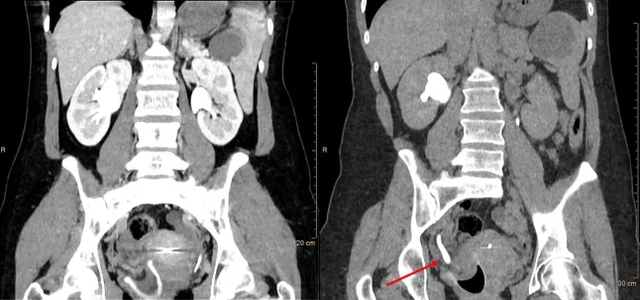

Bởi vì khi tới bệnh viện, Sarah cũng chỉ cho rằng mình bị sỏi thận tái phát. Nhưng kết quả chụp cắt lớp tiết niệu khiến các bác sĩ bất ngờ: thận phải và niệu quản của cô bị sưng đáng kể, với đường kính giãn nở lên đến 22mm. Nguyên nhân được xác định là do cốc nguyệt san đặt sai vị trí, vô tình chặn đường lưu thông của nước tiểu. Điều này dẫn đến hiện tượng ứ nước thận, gây nhiễm trùng và đau đớn kéo dài.